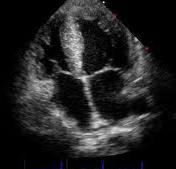

The TomTec integration with Impax is currently only intended for future distribution in Europe. The solution will deliver a smooth workflow oriented towards the off-line analysis of echocardiography images, from basic echo measurements to advanced left ventricle (LV) wall motion analysis, 4-D mitral valve analysis or right ventricle (RV).

The Impax review station provides fast and easy access to patient related image data for reviewing and direct reporting. In addition the TomTec integration offers advanced measurement functionality and 3-D, 4-D processing tools for cardiac and vascular ultrasound examinations for offline analyses. Both options function fully integrated with the Agfa Healthcare's CardioVascular Information System (CVIS), streamlining image review with structured clinical reporting.